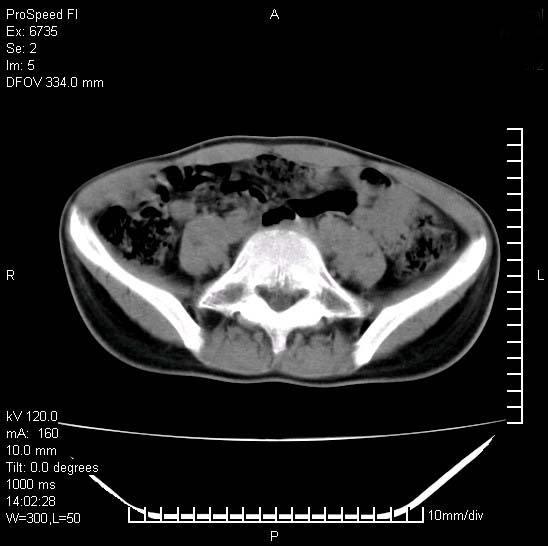

患者自诉胯部疼痛两年余,在当地服用中药,半月前至本院考虑骶髂关节结核,给予抗痨治疗。现发展至右下肢疼痛明显,活动受限,以膝关节处明显,拍膝关节平片无明显异常。

两侧骶骼关节改变,考虑强直性脊炎

左侧骶髂关节面限局性骨破坏,边缘硬化关节腔见钙化物;不出外tb

右侧骶髂关节也有类似改变,只是较左侧轻,首先考虑强直性脊柱炎,不除外结核,建议作hla-b27检查。

典型强脊炎改变,髋关节亦有累及

符合强直性脊柱炎表现。